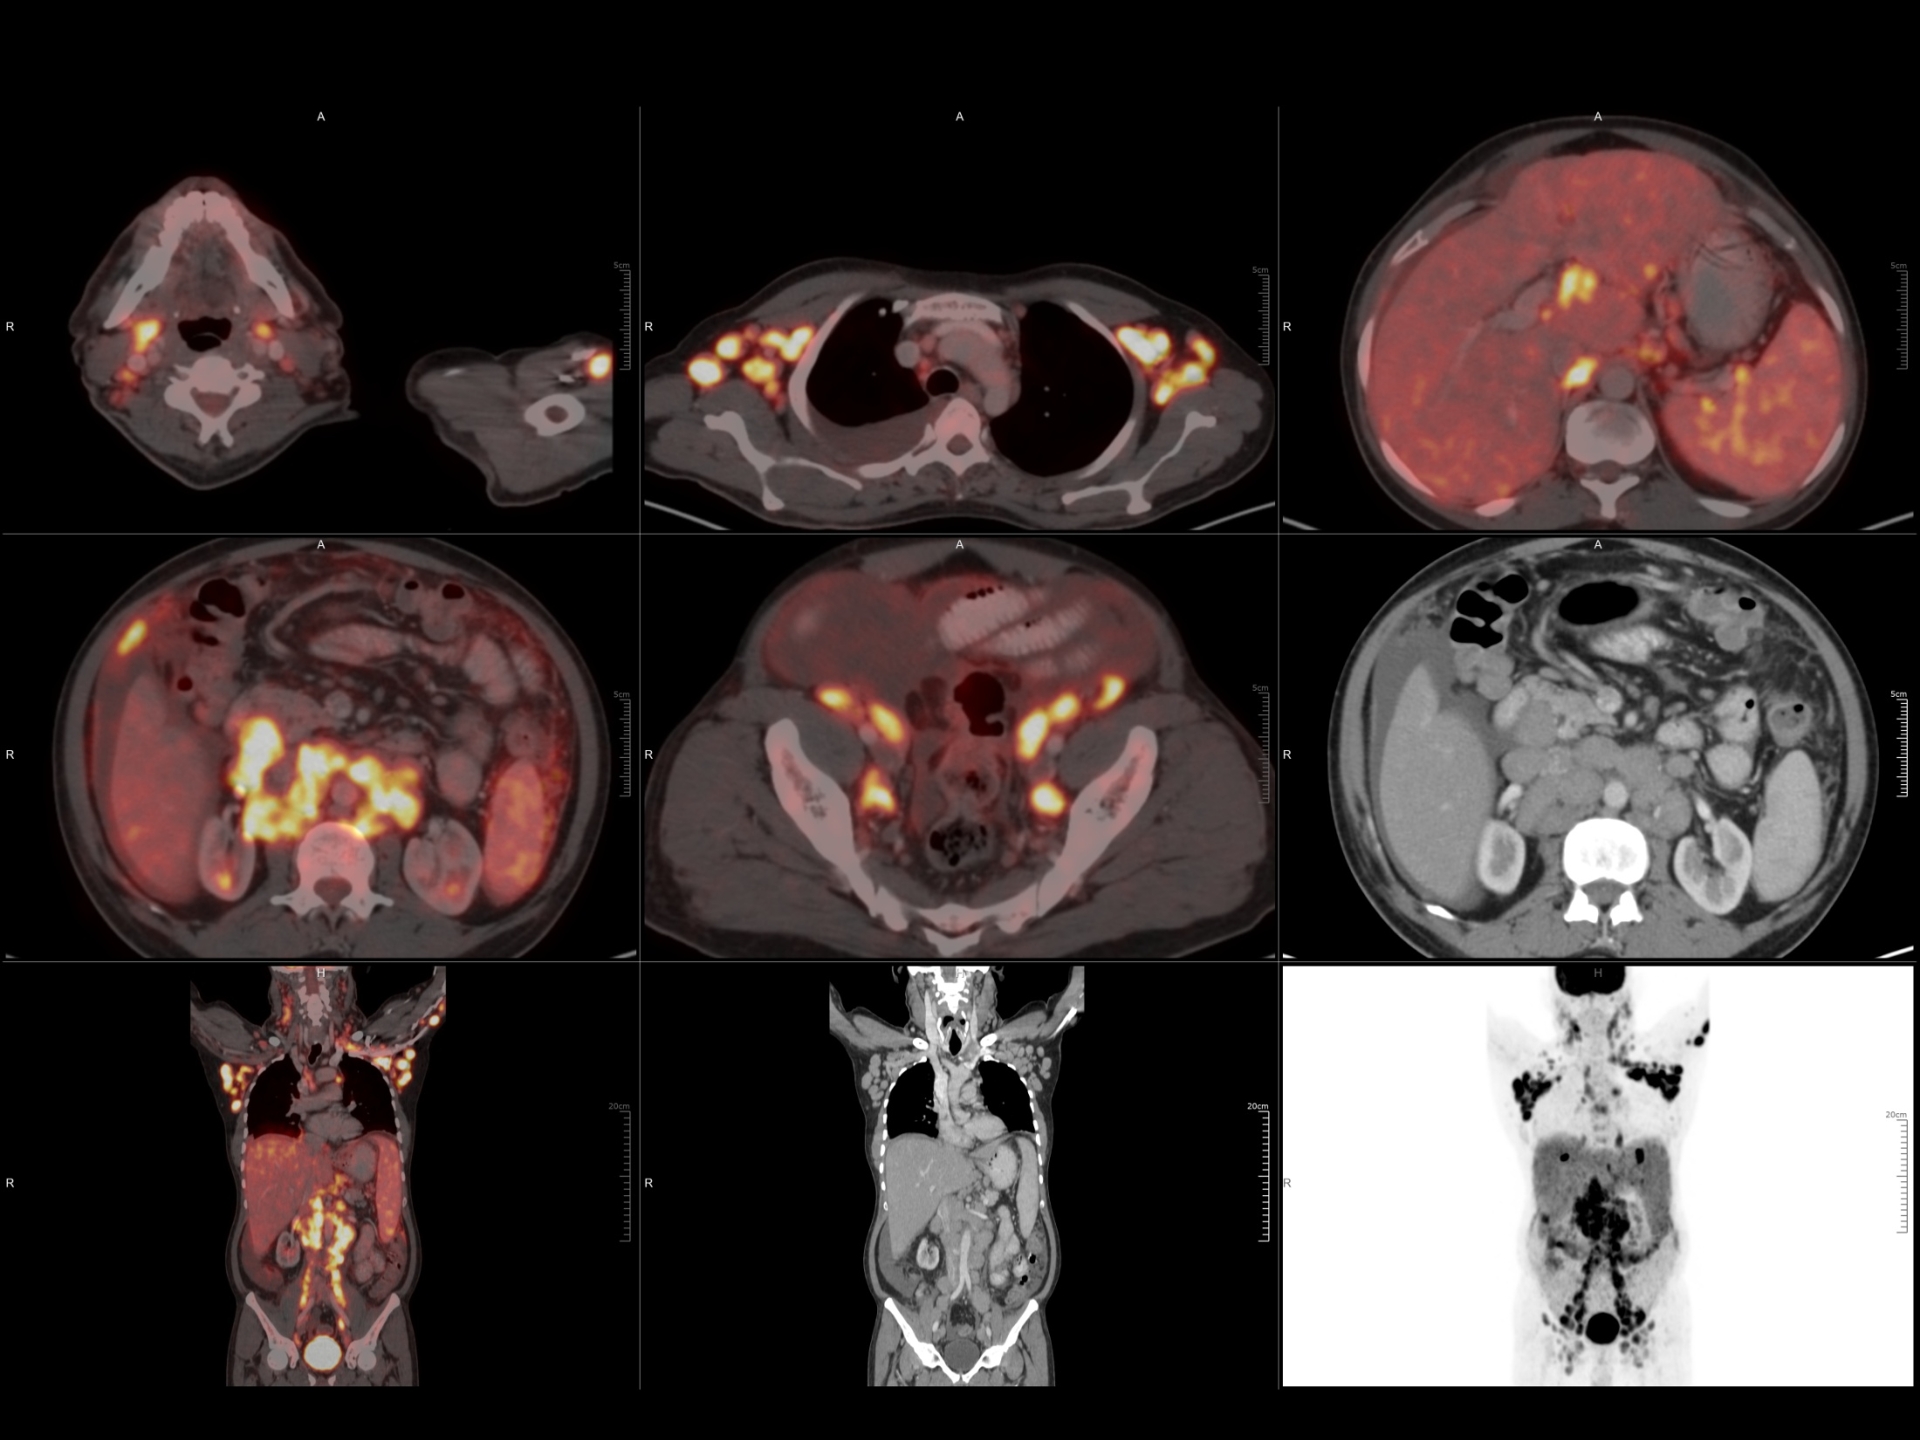

160 Slice Digital Pet-Ct

India’s first 160 slice High Resolution Digital PET-CT provides a revolutionary breakthrough in the combination of clarity, sensitivity, coverage and speed.

It takes just 5.5 minutes to complete the whole body scan.

It is possible to get very good quality images even with a very low dose of FDG (Radiation) and less time.

Sensitivity of detecting very small lesions (upto size of 5 mm) is very high.

Special scans like :

• PSMA for Prostate malignancy .

• Ga-DOTA to diagnose NET (Neuroendocrine tumors).